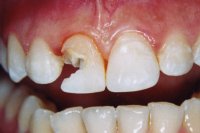

Ein seitlicher Oberkieferschneidezahn ist als sogenannter Zapfenzahn (angeboren) in die Mundhöhle durchgebrochen (Abb. 1). Nach orthodontischer Zahnbehandlung haben wir dem 16 Jahre alten Mädchen den Vorschlag gemacht, mittels zwei adhäsiv gelegten Kompositfüllungen und ohne Beschleifen den Zapfenzahn in einen natürlichen Schneidezahn umzuformen (Abb. 2).